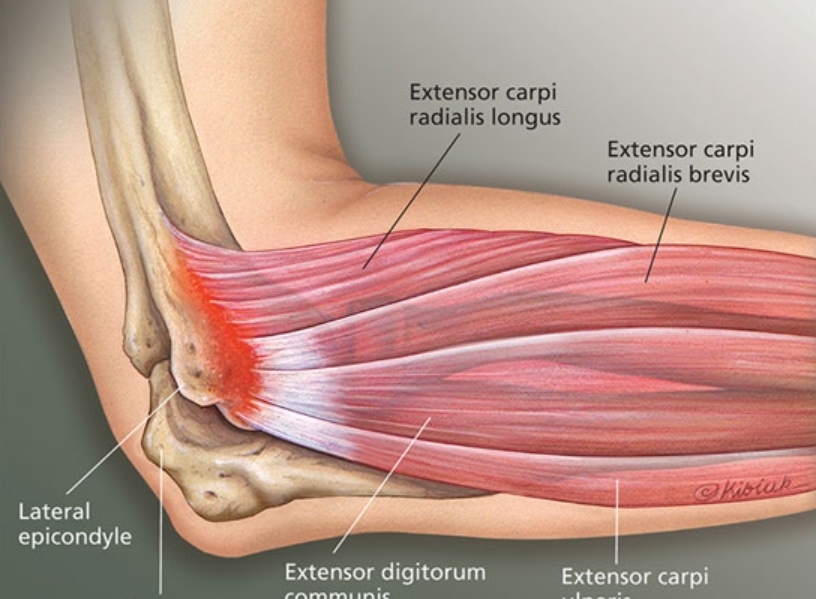

골프(테니스)엘보

팔꿈치 내외측통증을 보통 엘보라고 부릅니다. 직업이나운동과 관련된경우 잘 낫지않는경우가 있는데 보통 관절내 염증(관절염)을 동반하는 경우가 많습니다. 초음파로 쉽게 진단하고 치료가 가능합니다